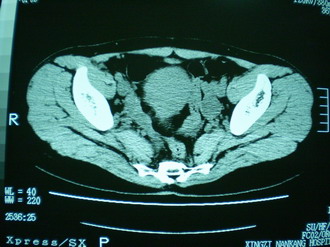

子宫增大,内可见类三角形低密度区,子宫后方可见类圆形团块状影,内部密度不均匀,可见靶样结构,结合病史考虑1子宫后方宫外孕(宫内假孕囊形成)2子宫肌瘤合并妊娠

子宫明显前倾,增大,宫颈增大呈分叶状。子宫直肠窝见不规则形水样低密度。(膀胱胀尿不理想)

考虑:1、宫颈部占位;

2、子宫直肠窝少量积液(盆腔炎所致)。

考虑:1、宫颈部占位(宫颈癌?);

2、子宫直肠窝少量积液。

1、前曲子宫,2、宫颈部占位?3、盆腔及右输卵管积液?宫内积血?4、左侧卵巢囊肿。